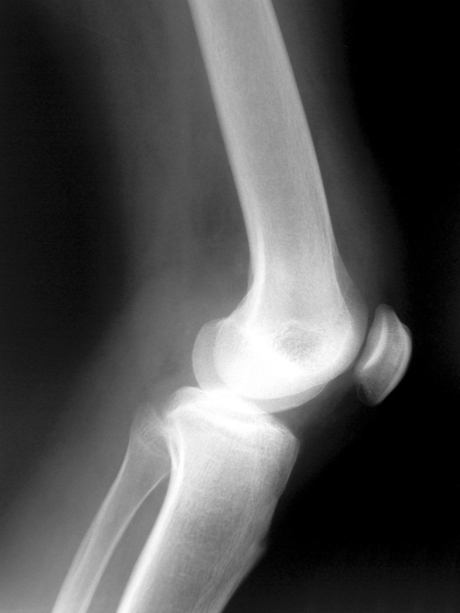

The research paper, published in the Journal of Tissue Engineering and Medicine, provides peer-reviewed support for an approach to regeneration of damaged cartilage within joints which is complementary to Orthocell’s current Ortho-ACI cartilage repair product.

The paper demonstrated that growth factors and extracellular matrix proteins derived from cells cultivated in a quality-controlled ‘cell factory’ — when concentrated and used as an intra-articular injection alone or combined with scaffolds — regenerated deep articular cartilage defects in New Zealand rabbits. No systemic cytotoxicity or inflammatory response was induced by any of the treatments.

“Histopathological analysis showed that rabbits treated with bioactive molecules alone had cartilage regeneration after 4 weeks,” the authors wrote. “However, rabbits treated with bioactive molecules along with scaffolds, with or without cells, showed cartilage formation after 3 weeks; 6 weeks after surgery, the cartilage regenerated in rabbits treated with either bioactive molecules alone or in combinations showed morphological similarities to native cartilage.”

According to Orthocell CEO Paul Anderson, “These bioreactor-produced native proteins have the potential to be a clinically important and cost-effective procedure for the regeneration of articular cartilage of the knee and also other joints.

“It may also be a promising early treatment in an ageing population with more widespread cartilage loss, such as those that occur in osteoarthritis,” he added.